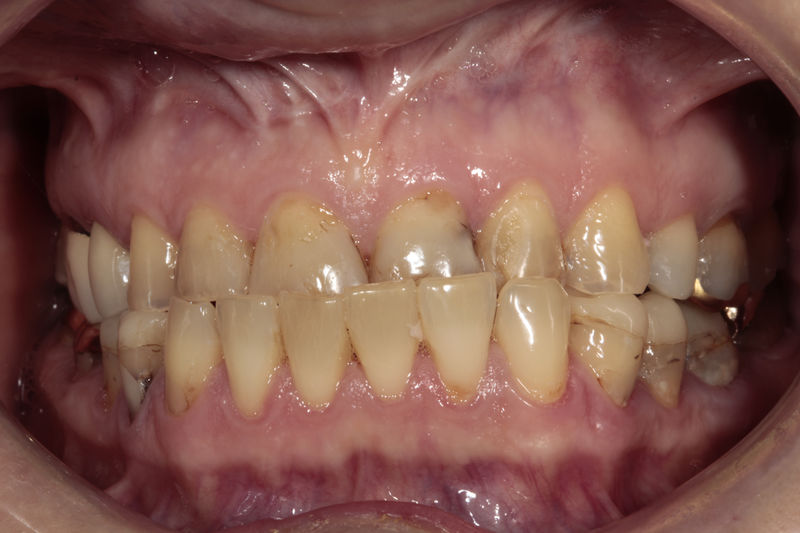

Disciplina fundamental de la Odontología enfocada en el diagnóstico, prevención y tratamiento restaurador de las piezas dentales que han sufrido daños. Su objetivo principal es devolver al diente su equilibrio biológico, funcional y estético cuando su integridad ha sido alterada. Resinas directas, incrustaciones, coronas.

Amplia gama de tratamientos para mejorar la apariencia de la sonrisa, corrigiendo el color, la forma, el tamaño, la alineación y la posición de los dientes. Los procedimientos más comunes y solicitados incluyen el blanqueamiento dental, las carillas y coronas, así como las resinas.